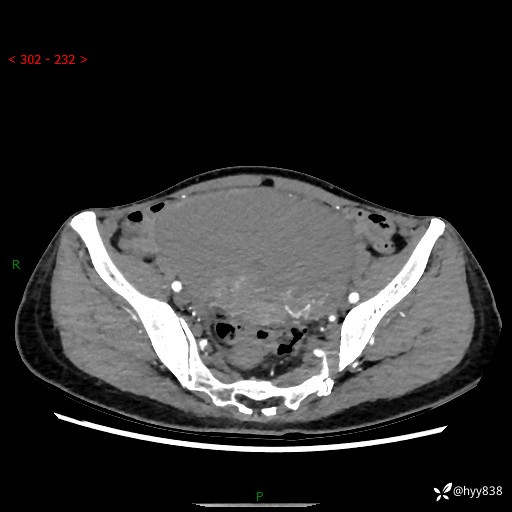

【患者信息】:女,50岁

【主诉】:外院超声发现腹盆肿块,为进一步诊治来我院,门诊已“盆腔肿块”收入院。

腹盆CT平扫+增强

【临床诊断】:盆腔肿瘤